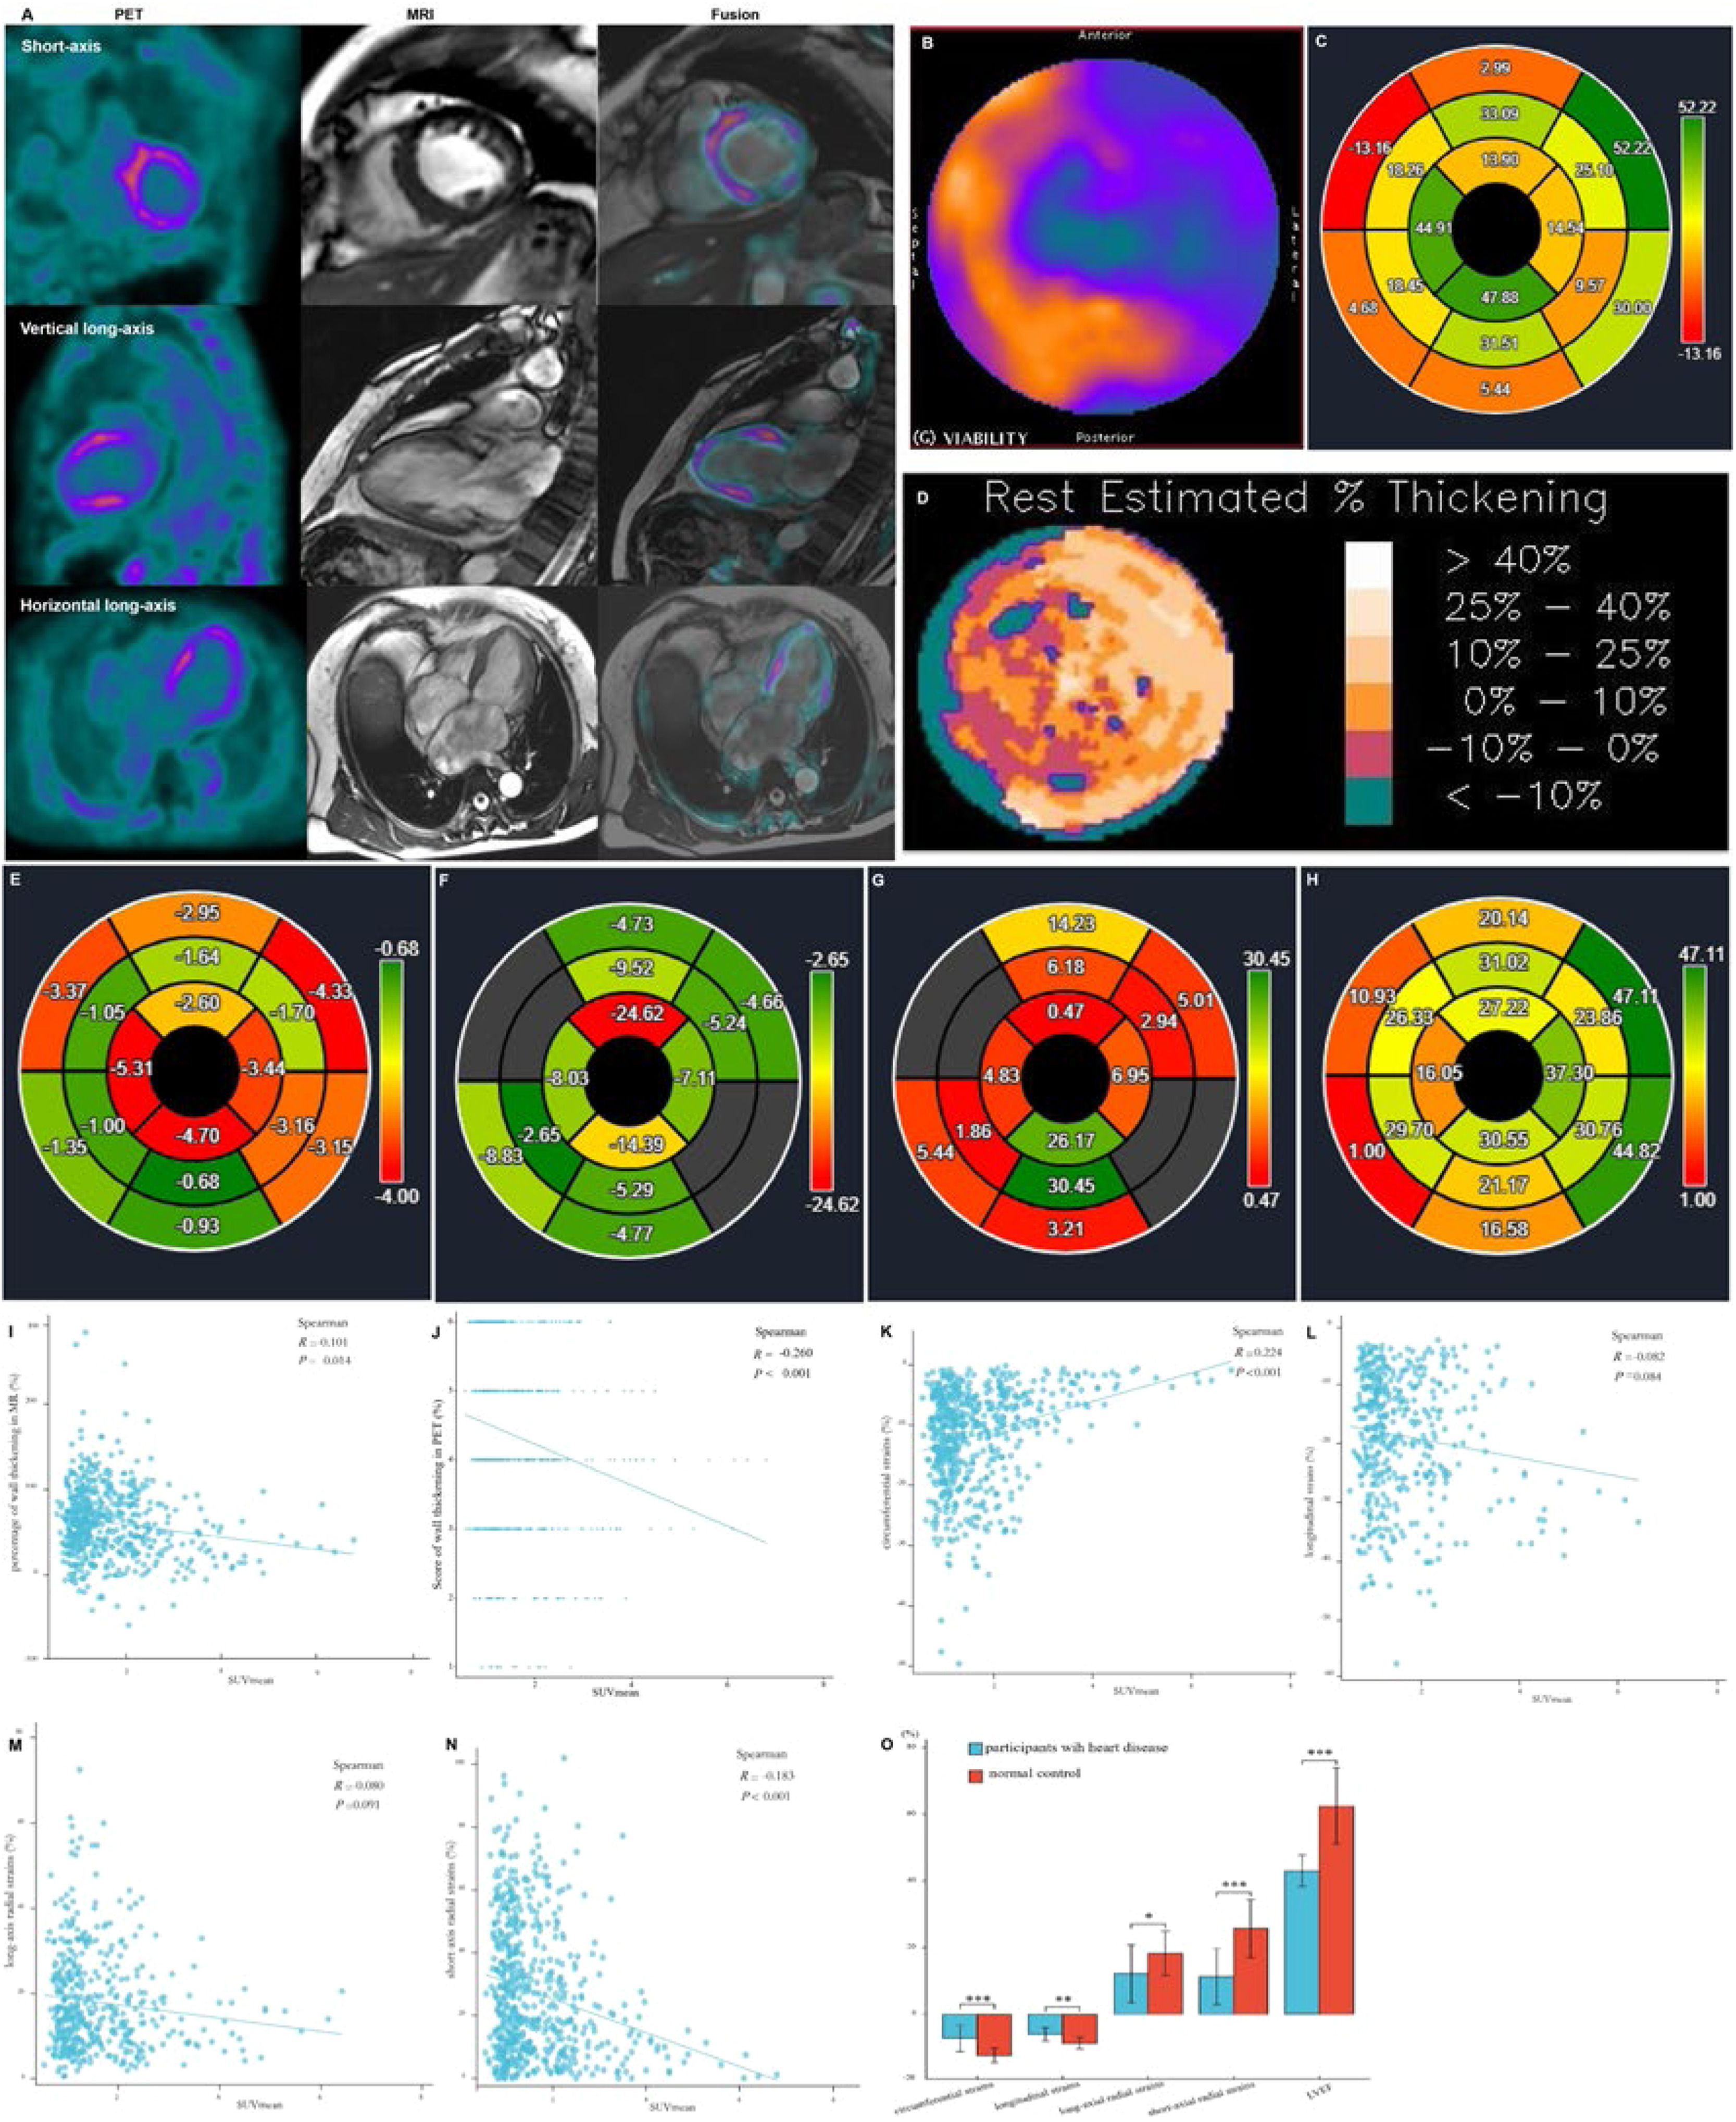

Except for the apical myocardium segment, data obtained from 592 myocardial segments in the polar map from the short-axis view of the cardiac PET/MR images of all participants were analyzed using statistical methods. Data on the FAPI distribution in the LV wall, percentage range of systolic wall thickening, percentage of systolic LV wall thickening, and peak myocardial strains in the 592 myocardial segments were visualized in the corresponding polar maps generated from the short-axis view of cardiac PET and MR images using the software (Fig. 2A‒H). A significant negative correlation was observed between SUVmean and score of systolic LV wall thickening in PET images (r = -0.260, p < 0.001) and SUVmean and percentage of systolic LV wall thickening in MR images (r = -0.101, p = 0.014). These findings indicate that increased FAPI uptake in the cardiac tissues was associated with decreased systolic LV wall thickening in the corresponding tissues, thereby reducing the magnitude of myocardial deformation of LV wall motion (Fig. 2I and 2J).

Images in a 64-year-old woman with multiple coronary stenosis (A‒H). 18F-AlF-FAPI PET images, MR images, and PET/MR fusion images in short-axis, vertical long-axis, and horizontal long-axis cine (A). The distribution of FAPI uptake in the polar map of PET images (B). There were higher FAPI uptake in the septum and inferior myocardium. The polar map of the percentages of systolic LV wall thickening per myocardial segment in MR images (C). The polar map of the percentage ranges of systolic LV wall thickening in PET images (D). Both C and D showed that the wall thickening decreased in the septum and inferior myocardium. The polar maps of the peak circumferential, longitudinal, long-axis radial and short-axis radial strains per myocardial segment in MR images (E‒H). The correlation analysis between the percentages and scores of systolic LV wall thickening, the peak circumferential, longitudinal, long-axis radial and short-axis radial strains and SUVmean in 16 myocardial segments from all participants (I‒N). There were significant negative correlation between SUVmean and the percentages (I) and scores (J) of systolic LV wall thickening, the peak circumferential (K) and short-axial radial strains (N), respectively. The comparison of the global circumferential, longitudinal, long-axis radial and short-axis radial strains and the Left Ventricular Ejection Fraction (LVEF) between all participants with heart diseases and normal ones (O). Each column represents mean ± SD. Asterisks indicate significant differences between them. * p < 0.05, ** p < 0.01, *** p < 0.001.

Furthermore, analysis of short- and long-axis CMR images demonstrated an inverse correlation between FAPI uptake in each segment and the peak circumferential and short-axial radial strains (SUVmean and circumferential strain: r = 0.224, p < 0.001; SUVmean and short-axis radial strain: r = -0.183, p < 0.001). With an increase in FAPI uptake in the cardiac tissues, the peak circumferential and short-axial radial strains in the corresponding tissues decreased. However, there were no significant differences in the correlations between the SUVmean and the peak longitudinal and long-axial radial strains in the same FAPI uptake segment (SUVmean and longitudinal strain: r = -0.082, p = 0.084; SUVmean and long-axis radial strain: r = -0.080, p = 0.091) (Fig. 2K‒N).

Comparative analysis of the global peak circumferential, longitudinal, long-axis radial and short-axis radial strains and LVEF between patients with heart disease and healthy controls revealed significant differences (circumferential strain: -7.38 ± 3.99 vs. -12.43 ± 2.14 [p < 0.001], longitudinal strain: -6.12 ± 1.99 vs. -8.82 ± 1.70 [p = 0.0014], long-axis radial strain: 12.14 ± 8.62 vs. 18.18 ± 6.66 [p = 0.0183], short-axis radial strain: 11.22 ± 8.40 vs. 25.70 ± 8.66 [p < 0.001], LVEF: 43.00 ± 4.74 vs. 62.47 ± 11.47 [p < 0.001]). Specifically, all global peak strains and LVEF were significantly lower in patients with heart disease than in healthy controls (Fig. 2O).